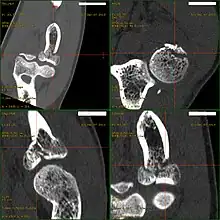

CT scan demonstrating the Mason type III radial head fracture -